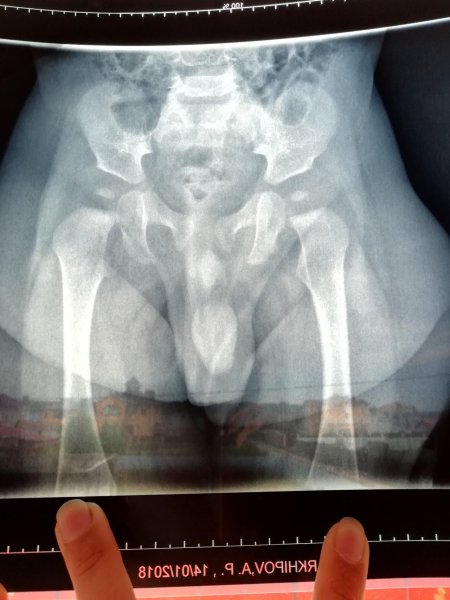

Рентгеновский эффект создает фантастические композиции в этих фотографиях девушки, чье тело становится прозрачным, демонстрируя скелет и внутренние органы. Она позирует в разных позах, ее силуэт светится загадочным свечением. Каждый кадр передает атмосферу научной фантастики и медицинского искусства. Ее кожа кажется полупрозрачной, позволяя увидеть кости и мышцы. Фотографии рассказывают о хрупкости человеческого тела и его внутренней красоте. Девушка то стоит в задумчивости, то делает грациозное движение. Эти иллюстрации вдохновляют на размышления о человеческой анатомии и уязвимости. Каждая картинка - это момент прозрения, когда внешнее уступает место внутреннему. Девушка воплощает образ современной Медузы, сочетающей красоту и загадочность.

Сквозь материю: тайны анатомии